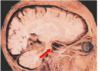

What type of herniation is depicted by the arrow? [1] Uncal Central (transtentorial) Cingulate (Subfalcine) Transcalvarial Upward cerebellar (transtentorial) Downward cerebellar (Tonsillar)

**Uncal** Central (transtentorial) Cingulate (Subfalcine) Transcalvarial Upward cerebellar (transtentorial) Downward cerebellar (Tonsillar)

What type of herniation is depicted? Uncal Central (transtentorial) Cingulate (Subfalcine) Transcalvarial Upward cerebellar (transtentorial) Downward cerebellar (Tonsillar)

What type of herniation is depicted? **Uncal** Central (transtentorial) Cingulate (Subfalcine) Transcalvarial Upward cerebellar (transtentorial) Downward cerebellar (Tonsillar) Uncal herniation. Arrows point to the medial temporal lobe that has herniated through the tentorial incisura to compress the midbrain